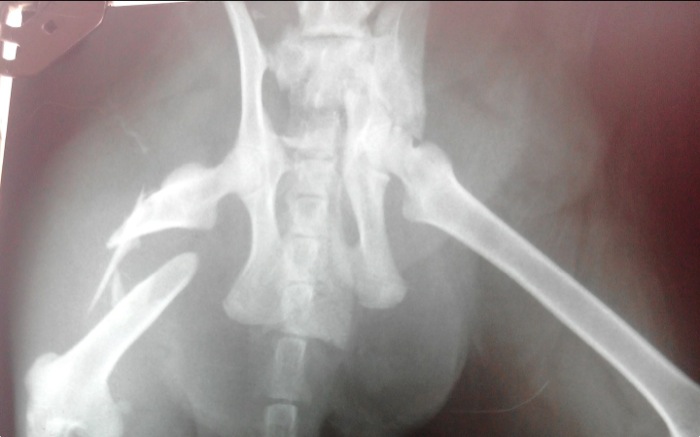

| Pruebas | La imagen radiográfica indica una fractura diafisaria de fémur con varios fragmentos, luxación sacroilícaca del mismo lado y fractura de ileon contralateral. A raíz de ello queda una estenosis secundaria del canal pélvico. |

Proyección ventrodorsal de cadera donde se aprecian las fracturas múltiples de fémur, púbis, isquion y fractura media de ileon con luxación del ileon derecho.